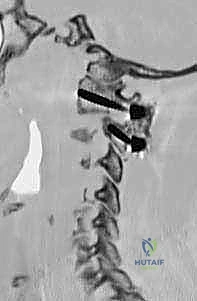

- التصوير المقطعي المحوسب (CT Scan) ثلاثي الأبعاد: وهو الفحص الأهم لتخطيط الجراحة. يعطي الدكتور هطيف خريطة دقيقة لتشريح العظام، حجم الكتل المفصلية، ومسار الشريان الفقري، مما يسمح له باختيار حجم ومسار المسامير بدقة المليمتر.

الخطوة 4: إدخال المسامير في الفقرة الأولى (C1 Lateral Mass Screws)

يتم تحديد نقطة الدخول على الكتلة المفصلية للفقرة C1. باستخدام مثقاب عالي السرعة (High-speed burr) ثم مثقاب يدوي دقيق، يتم عمل مسار للمسمار. يتم توجيه المسار بدقة ليكون موازياً للقوس الأمامي ومتجهاً قليلاً للداخل نحو مركز الفقرة لتجنب الشريان الفقري الذي يقع في الخارج. يتم إدخال مسمار من التيتانيوم (عادة بقطر 3.5 مم) في كل جانب.

الخطوة 5: إدخال المسامير في الفقرة الثانية (C2 Pedicle/Pars Screws)

بنفس الدقة، يتم تحديد نقطة الدخول في الفقرة C2. اعتماداً على التشريح الفردي للمريض (الذي تمت دراسته مسبقاً عبر الأشعة المقطعية)، يختار الدكتور هطيف إما مسار العنيقة (Pedicle) أو مسار الجزء البين مفصلي (Pars). يتم إدخال المسامير بزاوية محددة لضمان أقصى قوة تثبيت دون اختراق القناة الشوكية أو ثقبة الشريان الفقري.